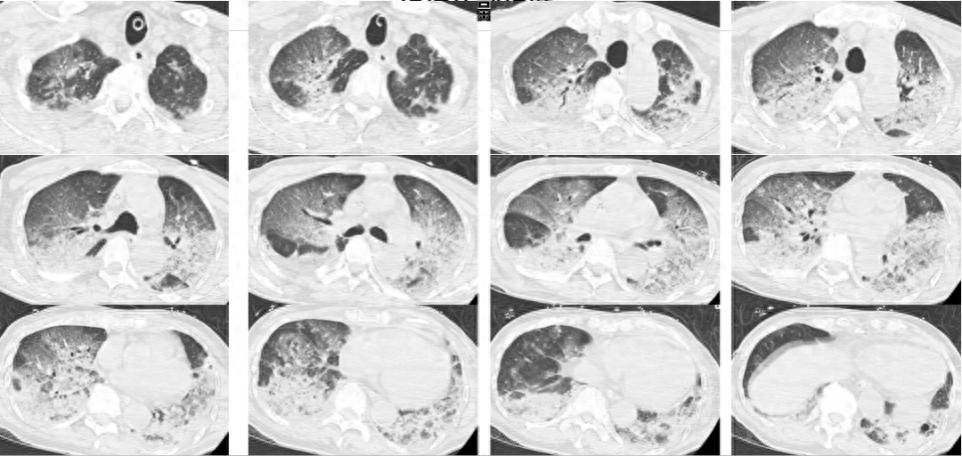

韩大爷的病情在就诊时十分严重。他处于意识模糊状态,生命体征极度不稳定。血压显著降低,心率下降至每分钟30次,血氧饱和度在80%至90%之间波动。血气分析显示pH值为7.094,二氧化碳分压达到77.4mmHg,这表明可能出现了Ⅱ型呼吸衰竭和呼吸性酸中毒。医生初步推测病因可能是肺栓塞或脑梗塞。现场情况危急,韩大爷身体极度虚弱,躺在病床上,生命安全处于高度危险之中。面对这一紧急情况,医生立即启动了抢救流程,对韩大爷进行了全面的病因检查。

医生根据检查所得数据对病因进行了详尽的分析。他们首先排除了中风和肺栓塞的可能性。在接受了积极的治疗后,韩大爷的体检结果有了明显改善。然而,尽管如此,韩大爷的白肺症状原因尚未查明,这一问题持续对医生构成挑战。